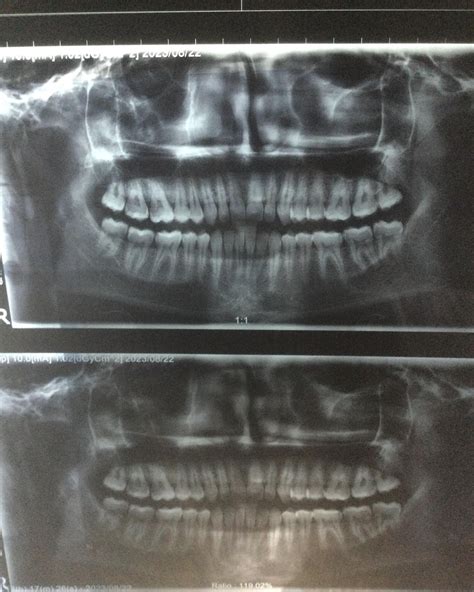

Regular dental check-ups, including digital X-rays, are the only way to monitor the development and positioning of your wisdom teeth. X-rays allow your dentist to see exactly how your teeth are growing beneath the surface, even before they begin to erupt through the gum. Early detection through routine screening allows for proactive planning, rather than waiting for an emergency situation to arise.